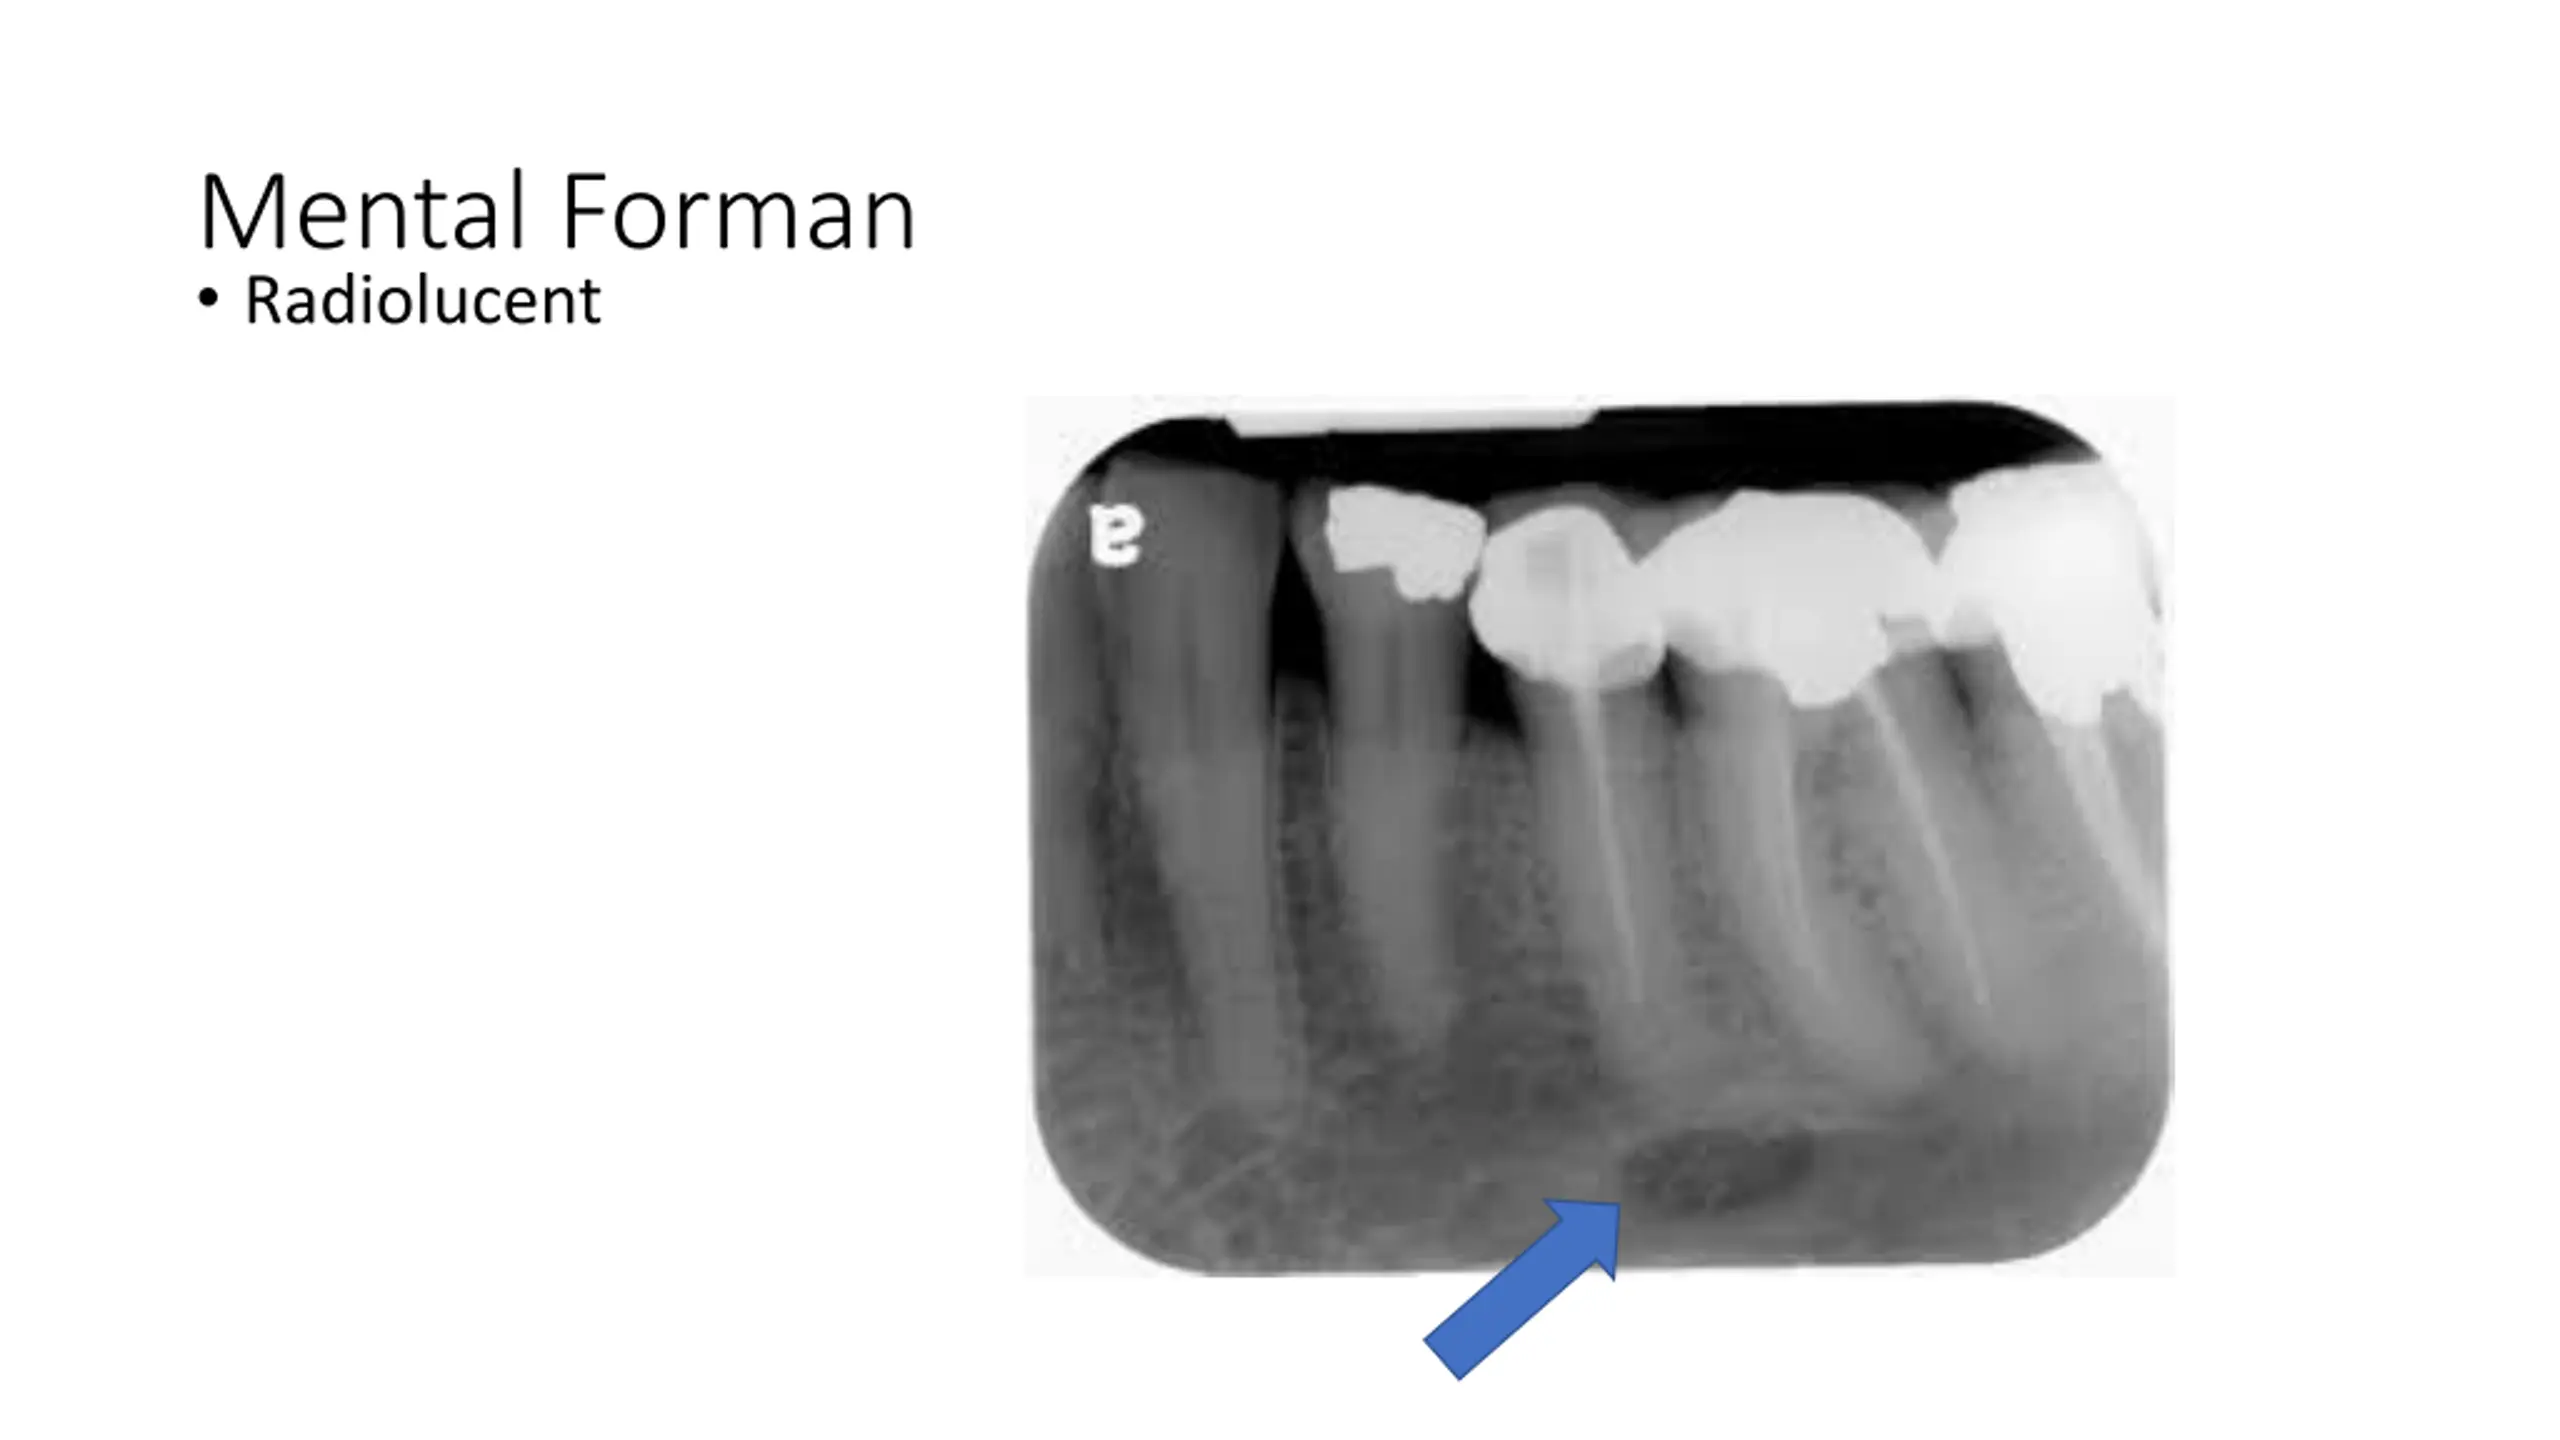

Mental Forman Radiolucent